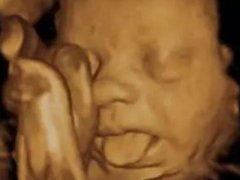

胎宝宝竟在妈妈肚子里做这么多事

四维彩超那么贵不懂这些就白做了